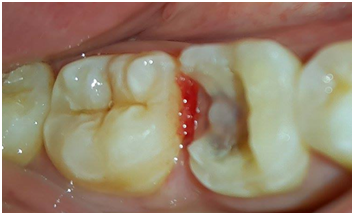

On the buccal surface of the restoration, the margins were located 0.5mm sub-gingivally for esthetic reasons and supra-gingivally on the lingual side. All sharp edges were rounded and smoothed (Figure 3). After a double gingival cord retraction, a simultaneous double mixed impression was made using light and heavy silicon A (Figure 4).

Figures 3 Tooth preparation.